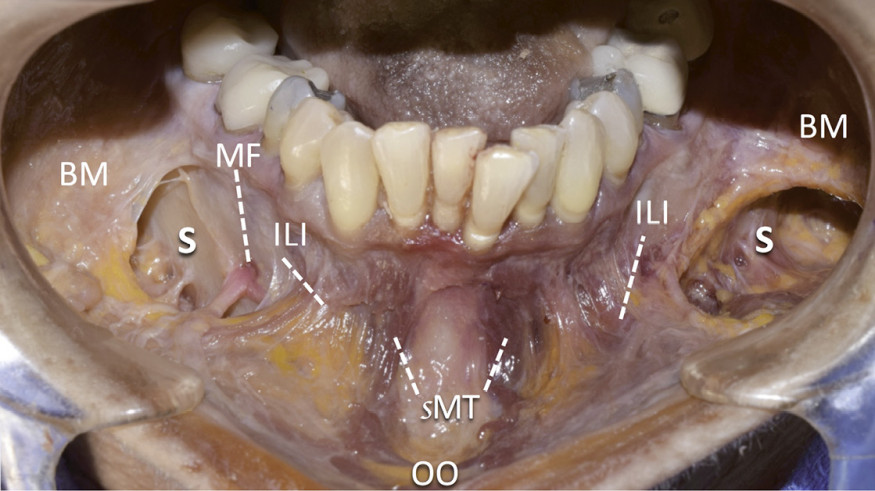

Rappels anatomiques (fig. 1)